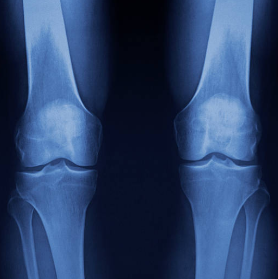

1. 무릎 연골 손상이란 무엇인지부터 쉽게 이해하기

무릎에는 뼈가 서로 부딪히지 않도록 도와주는 “연골”이 있어요.

대표적으로 두 가지가 중요합니다.

첫째, 관절연골

무릎뼈 끝을 매끈하게 감싸서 마찰을 줄여주고 충격을 흡수해요.

둘째, 반월상연골(반달연골)

무릎 안쪽과 바깥쪽에 있는 반달 모양의 연골로, 체중이 한쪽에 쏠리지 않도록 분산해 주는 역할을 해요.

이 연골이 닳거나 찢어지거나 손상되면 무릎이 뻣뻣하고 아프고, 걷는 자세까지 달라지면서 다른 관절까지 무리가 가기 쉬워요.

연골은 혈관이 거의 없어서 “피가 통하면서 빨리 낫는 조직”이 아니에요. 그래서 작은 손상도 그냥 넘기지 말고, 초기에 관리해 줘야 회복이 훨씬 수월합니다.